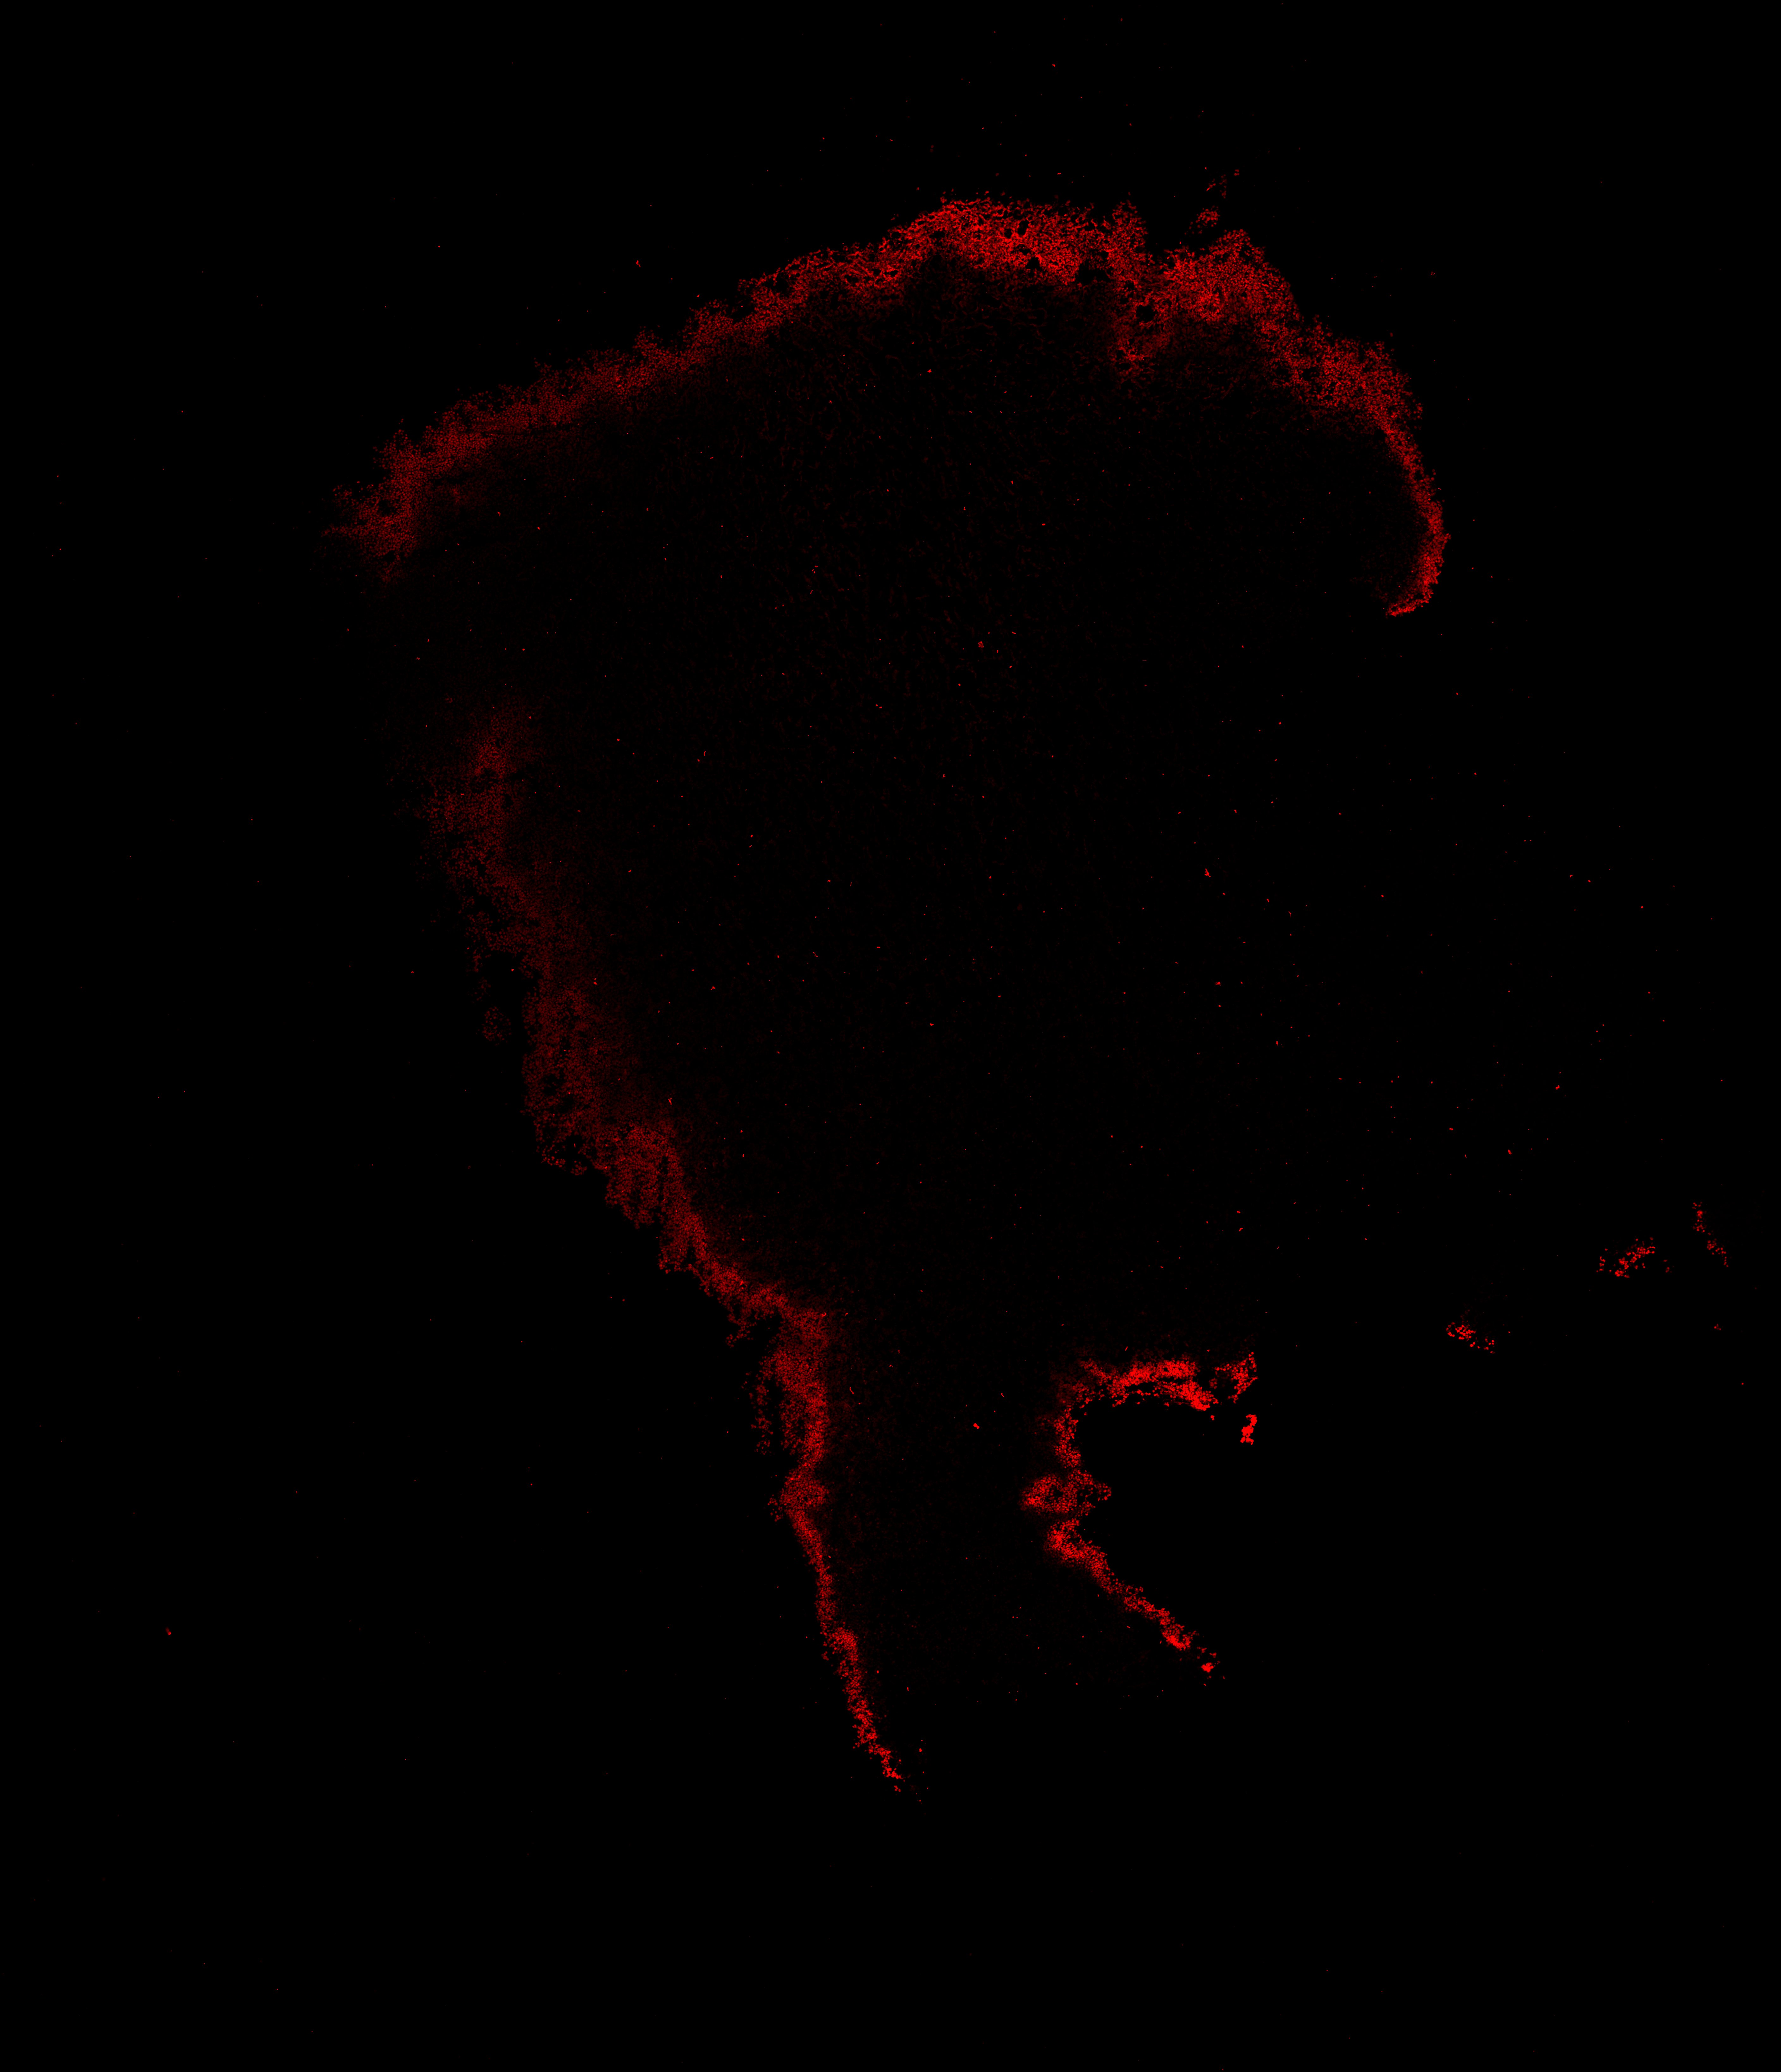

TH

6PCW human midbrain